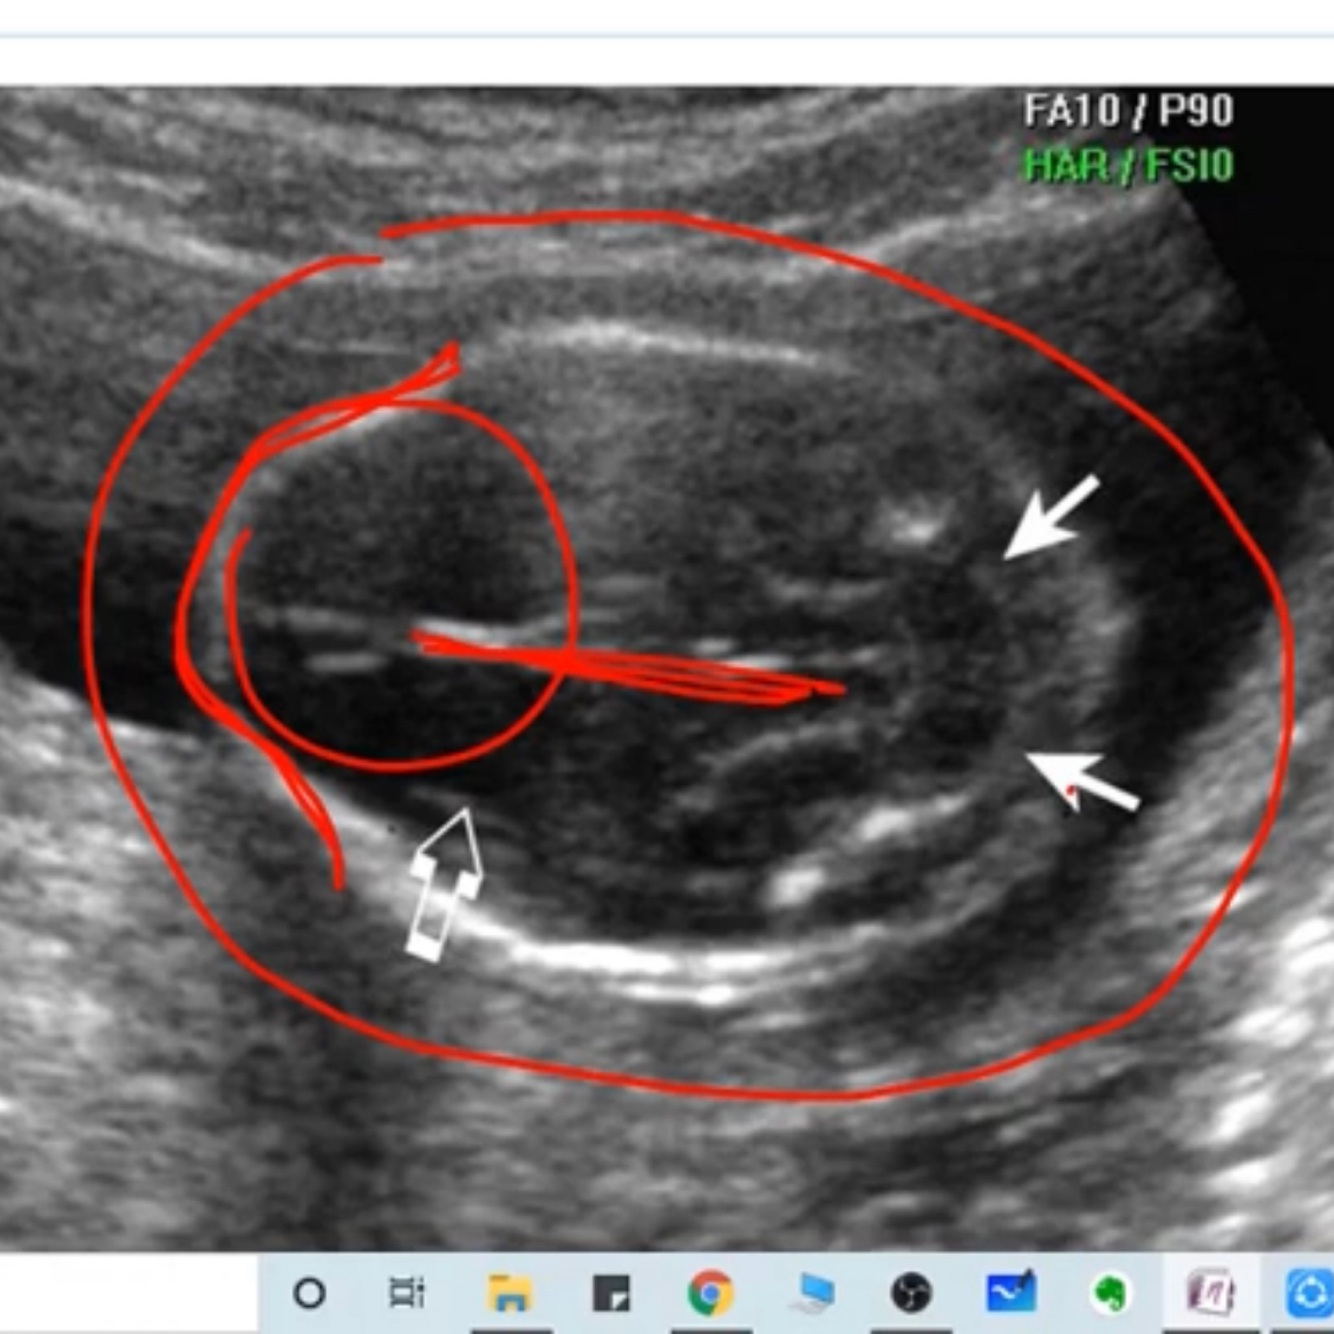

Lemon and banana sign of Spina bifida

A

Lemon: frontal bone scalloping, because chiari

Banana: flattened cerebellum looks like a banana